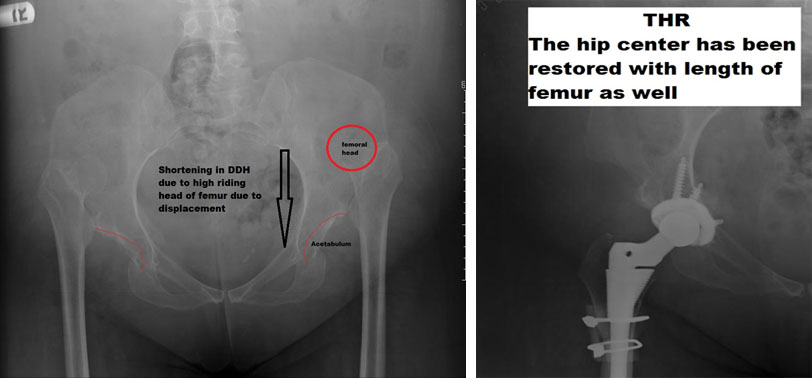

DDH is a condition where the hip is congenitally or from an early age outside the pelvic socket piece.

Unique points of THR in DDH-

- Need special implants for this surgery and requires extensive surgical planning like a 22.5 mm head of the femur.

- Needs femoral shortening and possible bone grafting on the acetabular sidev

- The femur has increased anteversion ( the angle between the neck and the stem of bone), shorter neck, and the cavity of the bone is narrow. These anatomical features make it necessary that an appropriate stem is used to fill the canal; otherwise can lead to surgeon induced errors.

- Dislocation after DDH surgery is in the range of 6-10% because there is a tiny femoral head with significant soft tissue dissection for the surgery.

- Sciatic Nerve palsy might be a significant complication as the soft tissue around the hip joint is stretched out, as the joint is relocated.